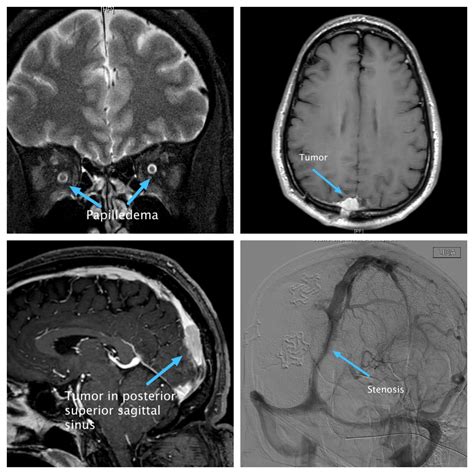

Because the Superior Sagittal Sinus serves as a primary drainage pathway, any obstruction or pathology within this vessel can have severe consequences for brain health. Clinical conditions associated with this sinus are generally categorized under cerebral venous thrombosis (CVT) or related to increased intracranial pressure.

• Cerebral Venous Thrombosis (CVT): The formation of a blood clot within the sinus, which can lead to venous infarction, hemorrhage, and elevated intracranial pressure. Symptoms often include severe headaches, seizures, and focal neurological deficits.

Diagnostic Imaging and Evaluation

Evaluating the Superior Sagittal Sinus is a standard part of neuroimaging protocols when venous pathology is suspected. Advances in radiological technology have made it much easier to visualize the patency and flow dynamics of the sinus without invasive procedures.

• CT Venography (CTV): Uses contrast dye to provide high-resolution images of the venous structures. It is highly effective for identifying acute thrombus formation.

• Magnetic Resonance Venography (MRV): A non-invasive method that does not require radiation. It is excellent for visualizing the flow within the Superior Sagittal Sinus and detecting slow flow or obstructions.

• Digital Subtraction Angiography (DSA): While more invasive, it remains the "gold standard" for complex cases, especially when planning surgical or endovascular interventions for fistulas or severe thrombosis.

When clinicians analyze these images, they look for specific signs, such as the "empty delta sign" in contrast-enhanced CT scans. This sign occurs when a thrombus occupies the lumen of the Superior Sagittal Sinus, causing the contrast to flow around the clot and create a triangular, empty-appearing area in the center of the sinus.